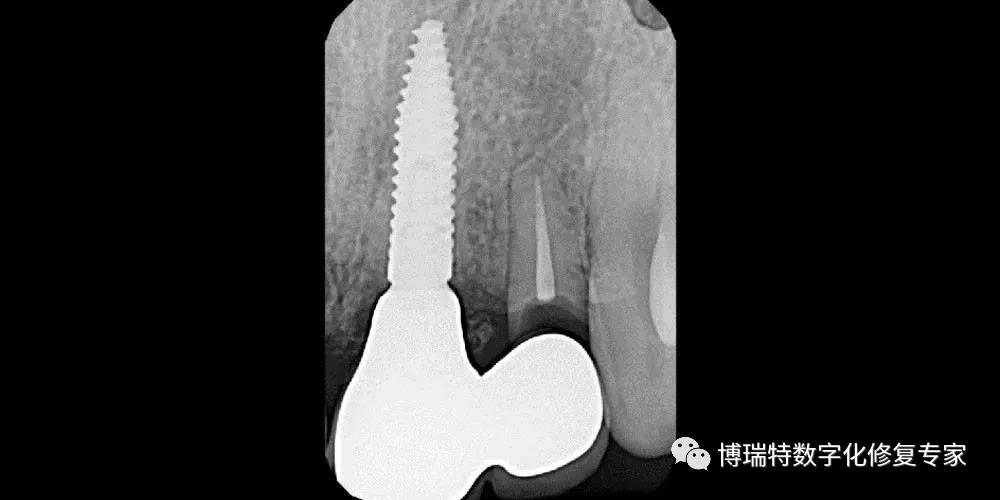

8226; CBCT检查显示11,12见根颈1/3根折线,无明显移位;

8226; 21根颈1/3根折,冠向移位,唇侧骨板完整,厚度约1mm,根尖区骨量充足;

8226; 22根长约9mm。

8226; 仔细探查唇侧骨壁,骨壁完整,偏腭侧制备种植窝洞,植入Straumann Roxolid® SLActive® BLT 3.3mm×14mm 种植体;

8226; 种植体三维位置良好,位于理想龈缘根方3mm-4mm;

8226; 种植体植入扭矩大于35N.cm;

8226; 种植体与唇侧骨板2mm以上的跳跃间隙,间隙内植入骨粉;

8226; 术后CBCT 。